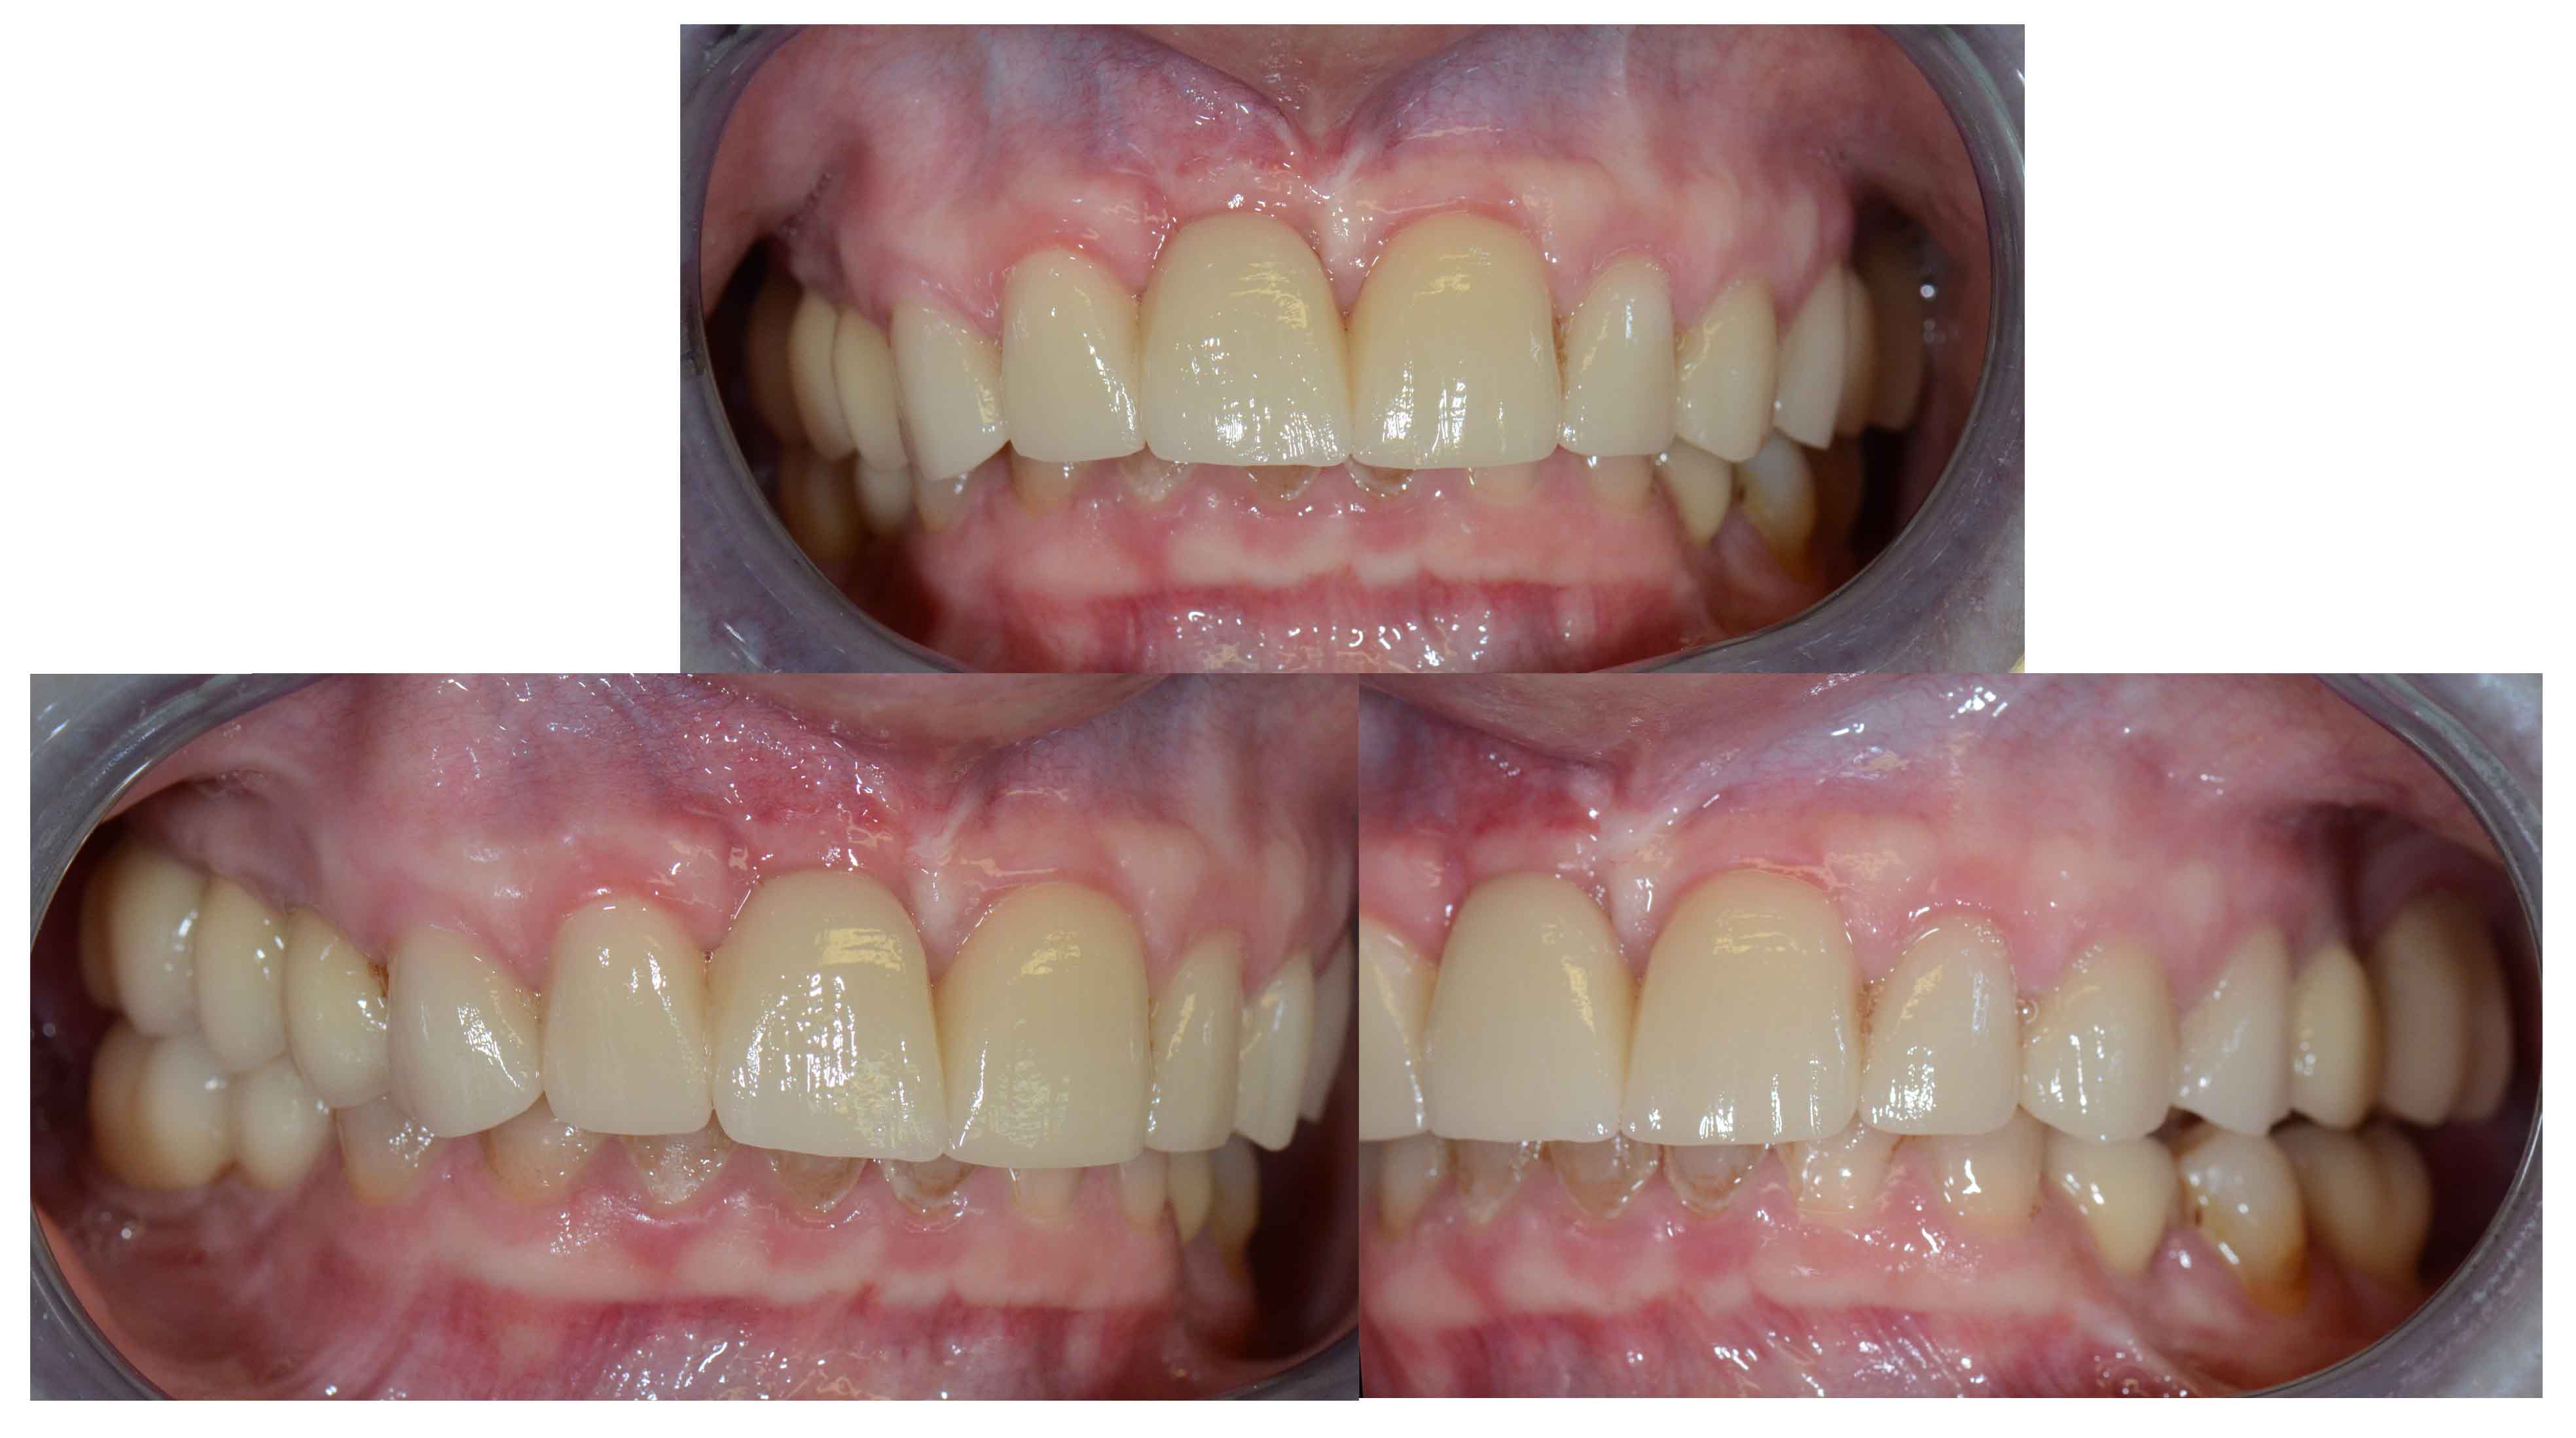

Tooth discoloration caused by tetracyclines

Aesthetic Rehabilitation with ceramic crowns and venners

Colour changes due to the use of tetracyclines as a child. Various treatments were done before to try to solve the problem but all of them were unsuccessful.

Full crowns were opted to cover the teeth that were very damaged and venners were used to cover those who were less damaged and by doing this less natural tooth structure was damaged.